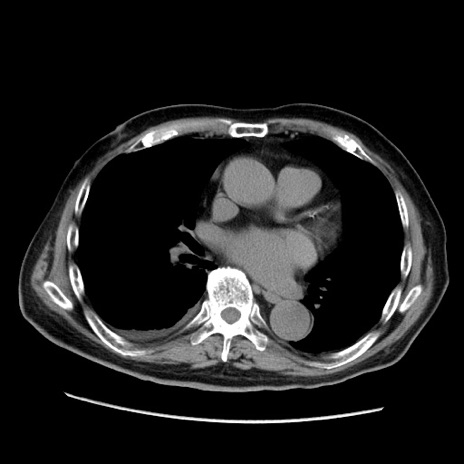

冠状断像

症例21(横断像)

【症例】70歳代男性

【主訴】腹痛

【現病歴】肝硬変・肝細胞癌にてかかりつけの方。約9時間前に食後より腹痛出現。症状が徐々に増悪し、嘔吐出現したため来院。

【既往歴】肝硬変、肝細胞癌(RFA、TACE後)

【身体所見】意識清明、表情苦悶様、BT 36℃、BP 129/78mmHg、P 88bpm、SpO2 97%(RA)、右上腹部から心窩部にかけて圧痛あり、反跳痛なし、筋性防御あり。

【データ】WBC 5800、CRP 0.16